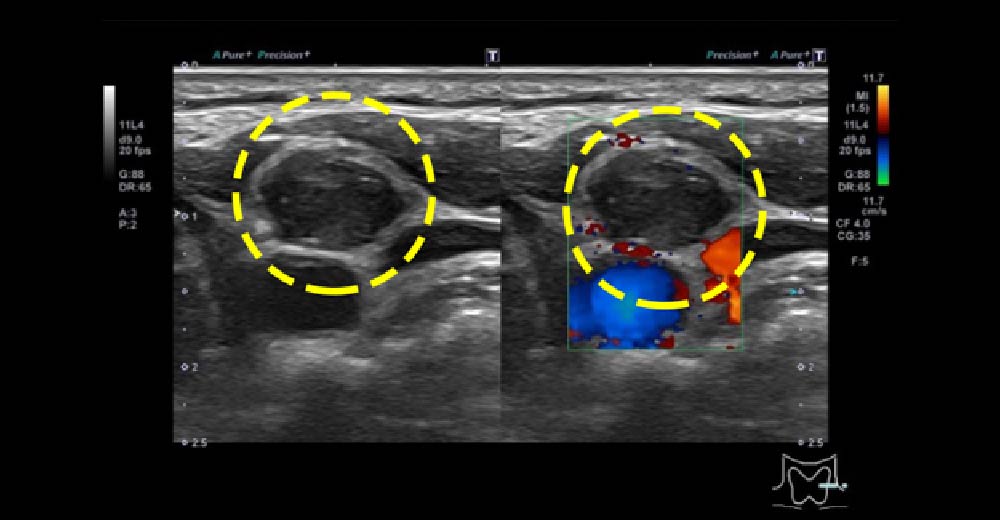

甲状腺乳頭がん

甲状腺右葉に境界不整、辺縁不整、内部不均一で一部石灰化を伴い、長径30mm程度の内部血流を伴う腫瘤を認めます。甲状腺全摘に至りました。

甲状腺乳頭がん 甲状腺乳頭がん